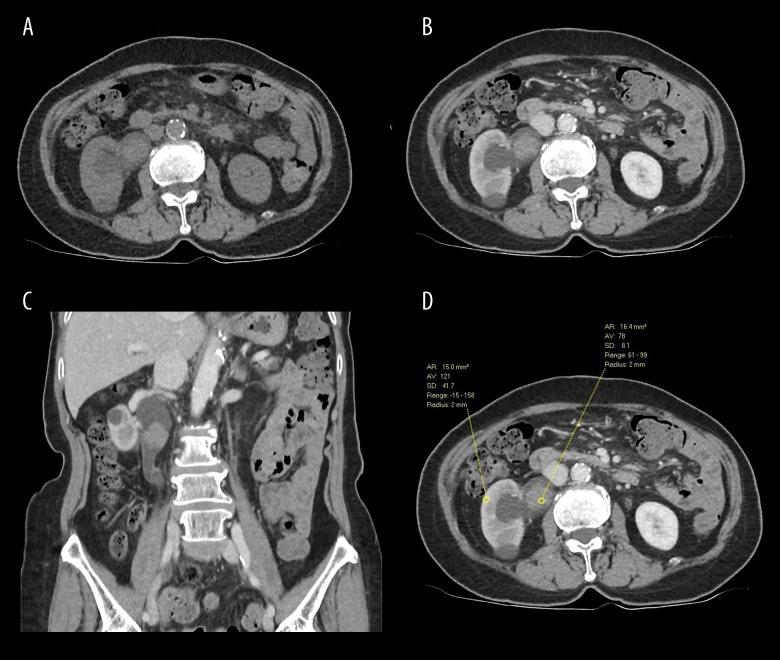

BACKGROUND Preoperative differentiation between renal cell carcinoma (RCC) and transitional cell carcinoma (TCC) is of utmost important for determining surgical strategy, whether nephrectomy or nephro-ureterectomy, as well as the necessity for wider lymphadenectomy and subsequent intensive surveillance, as the latter is more prone to recurrence. CASE REPORT A 76-year-old Chinese woman presented with flank pain and gross hematuria, and was found to have right-sided hydronephrosis. An obstructing tumor in the renal pelvis was shown on a computed tomography (CT) intravenous pyelogram. Although its enhancement pattern was suggestive of RCC, the location within the collecting system without any attachment to the renal parenchyma is very unusual. The mass was diagnosed histopathologically as RCC on both ureteroscopic biopsy and subsequent radical nephrectomy. CONCLUSIONS We present a rare case of RCC growing exclusively in the renal pelvis, mimicking a TCC. Hypotheses regarding this unusual presentation include direct invasion, continuous implantation, and intraluminal transit down the collecting system. The characteristics on imaging studies, including greater enhancement and higher tumor-to-kidney attenuation ratio, may provide a clue for diagnosis, but ureteroscopy and histopathology are the criterion standards and should be considered as part of routine preoperative assessment. Amidst controversies and inconsistencies, more and more emerging evidence suggests that RCC with urinary collecting system invasion is associated with less favorable overall and recurrence-free survival, especially in localized diseases.

一名 76 岁的中国女性因腰痛和肉眼血尿就诊,发现右侧肾盂积水。CT 静脉肾盂造影显示肾盂内有一个阻塞性肿瘤。尽管其增强模式提示为 RCC,但位于集合系统内而不与肾实质相连的位置非常罕见。该肿块在输尿管镜活检和随后的根治性肾切除术中均被组织病理学诊断为 RCC。

我们报告了一例罕见的完全在肾盂内生长的 RCC 病例,类似于 TCC。对于这种不常见表现的假设包括直接侵犯、连续种植和腔内通过集合系统。影像学研究的特征,包括更高的增强和更高的肿瘤与肾脏衰减比值,可能为诊断提供线索,但输尿管镜检查和组织病理学是标准标准,应作为常规术前评估的一部分考虑。在争议和不一致的情况下,越来越多的新证据表明,伴有尿收集系统侵犯的 RCC 与整体和无复发生存率较差相关,尤其是在局限性疾病中。